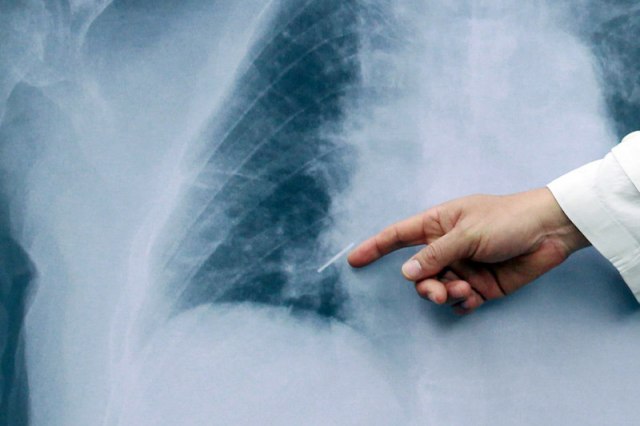

Ako je slučaj kovida 19 ozbiljan, pacijent će vrlo verovatno razviti sindrom akutnog respiratornog distresa (ARDS).